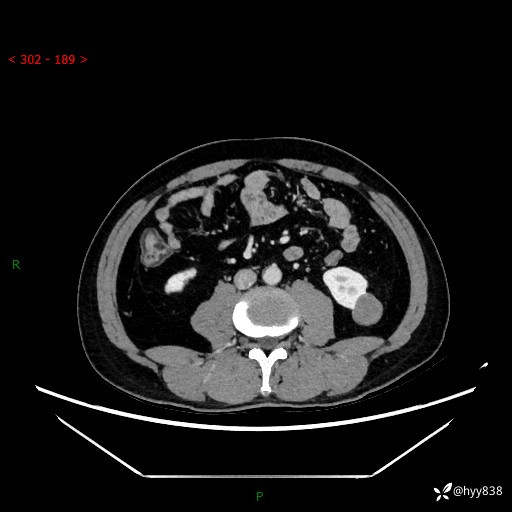

中年男性,左侧腰背部间断性胀痛不适。第一眼“乳头或囊肿”,有无意外---(有结果)

【患者信息】:41岁/男

【主诉】:左侧腰背部间断性胀痛不适1周

【现病史及既往史】:患者1周前无明显诱因出现左侧腰部疼痛,呈间断性胀痛,休息后可缓解,无放射痛,偶可见肉眼血尿,无血块,无尿频尿急尿痛,无夜尿增多,无畏寒发热、咳嗽咳痰等症状。于我院查双肾CT示:左肾占位性病变,左肾下极囊性病变,左肾轻度积水,胆囊多发结石。今为求进一步诊治来我院,门诊以“左肾占位性病变”收治入院。 起病以来,患者精神佳,饮食、睡眠良好,大便正常,小便如上诉,体力体重无明显变化。

【检查】:肾脏CT平扫+增强